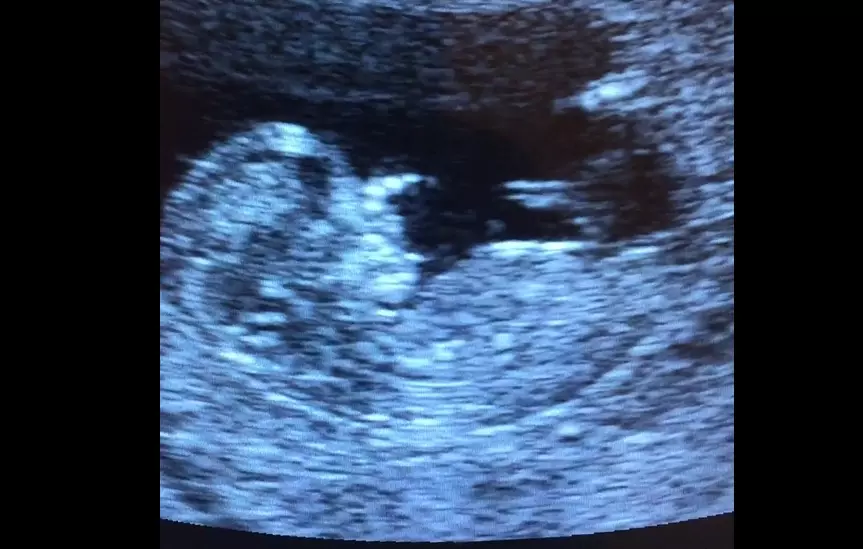

"It sounds like a heartbeat on an ultrasound, but it's not a fully-formed heart," Planned Parenthood now contends.

In the past, Planned Parenthood cited the American College of Obstetricians and Gynecologists (ACOG), whose "Guide to Language and Abortion" said that "a fetal heartbeat exists only after the chambers of the heart have developed and can be detected via ultrasound, which typically occurs around 17 to 20 weeks' gestation," National Review (NR) reports.